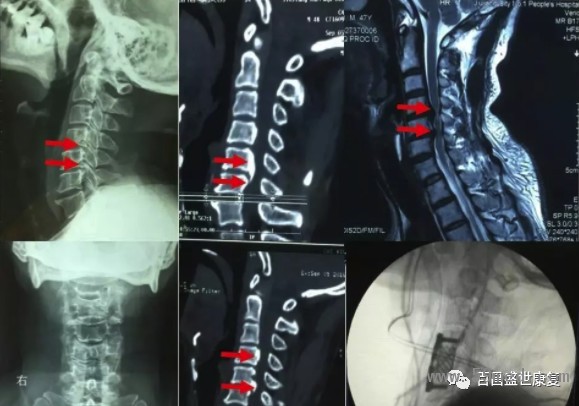

三、脊髓型頸椎病該型發(fā)病率不高,但因為其可能引起癱瘓,它是頸椎病中最嚴(yán)重,致殘率最高的類型。

患者出現(xiàn)單側(cè)或雙側(cè)上肢麻木,無力感,寫字,握筷等精細(xì)動作很難完成,手持物易脫落;單側(cè)或雙側(cè)下肢體乏力,沉重感,部分患者出現(xiàn)走路就像“踩在棉花”上一樣不踏實的感覺。

有的患者還會出現(xiàn)軀干部猶如皮帶捆綁樣的異常感覺;嚴(yán)重者出現(xiàn)大小便功能障礙,行走困難甚至發(fā)生癱瘓。

由于該型頸椎病起病隱匿,發(fā)作很緩慢,因此很多患者得不到及早診斷,就診時候已經(jīng)出現(xiàn)脊髓信號改變,從而導(dǎo)致不可逆性脊髓損傷。

因此對于此類型頸椎病患者,但凡有癥狀懷疑此型頸椎病時,早期頸椎核磁共振檢查十分必要,若核磁共振提示脊髓壓迫導(dǎo)致脊髓信號改變,應(yīng)該盡快實施手術(shù)。